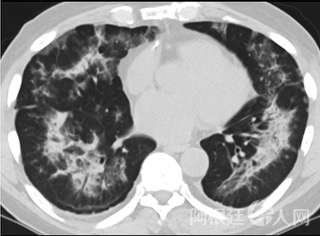

6天后的轴向CT平扫图像显示毛玻璃影变为实变和轻度结构扭曲。(同一病人CT影像)

16位被文献报道为电子烟肺炎的患者被专家判定为“病毒性感染”,即有可能是新冠肺炎的“疑诊患者”,其中更有5位临床症状和治疗情况相对完整的患者被判定为“中度可疑”。因此在2019年美国报道的电子烟肺炎中存在病毒性感染的病例,而且不排除美国电子烟肺炎中存在新冠肺炎的可能性。